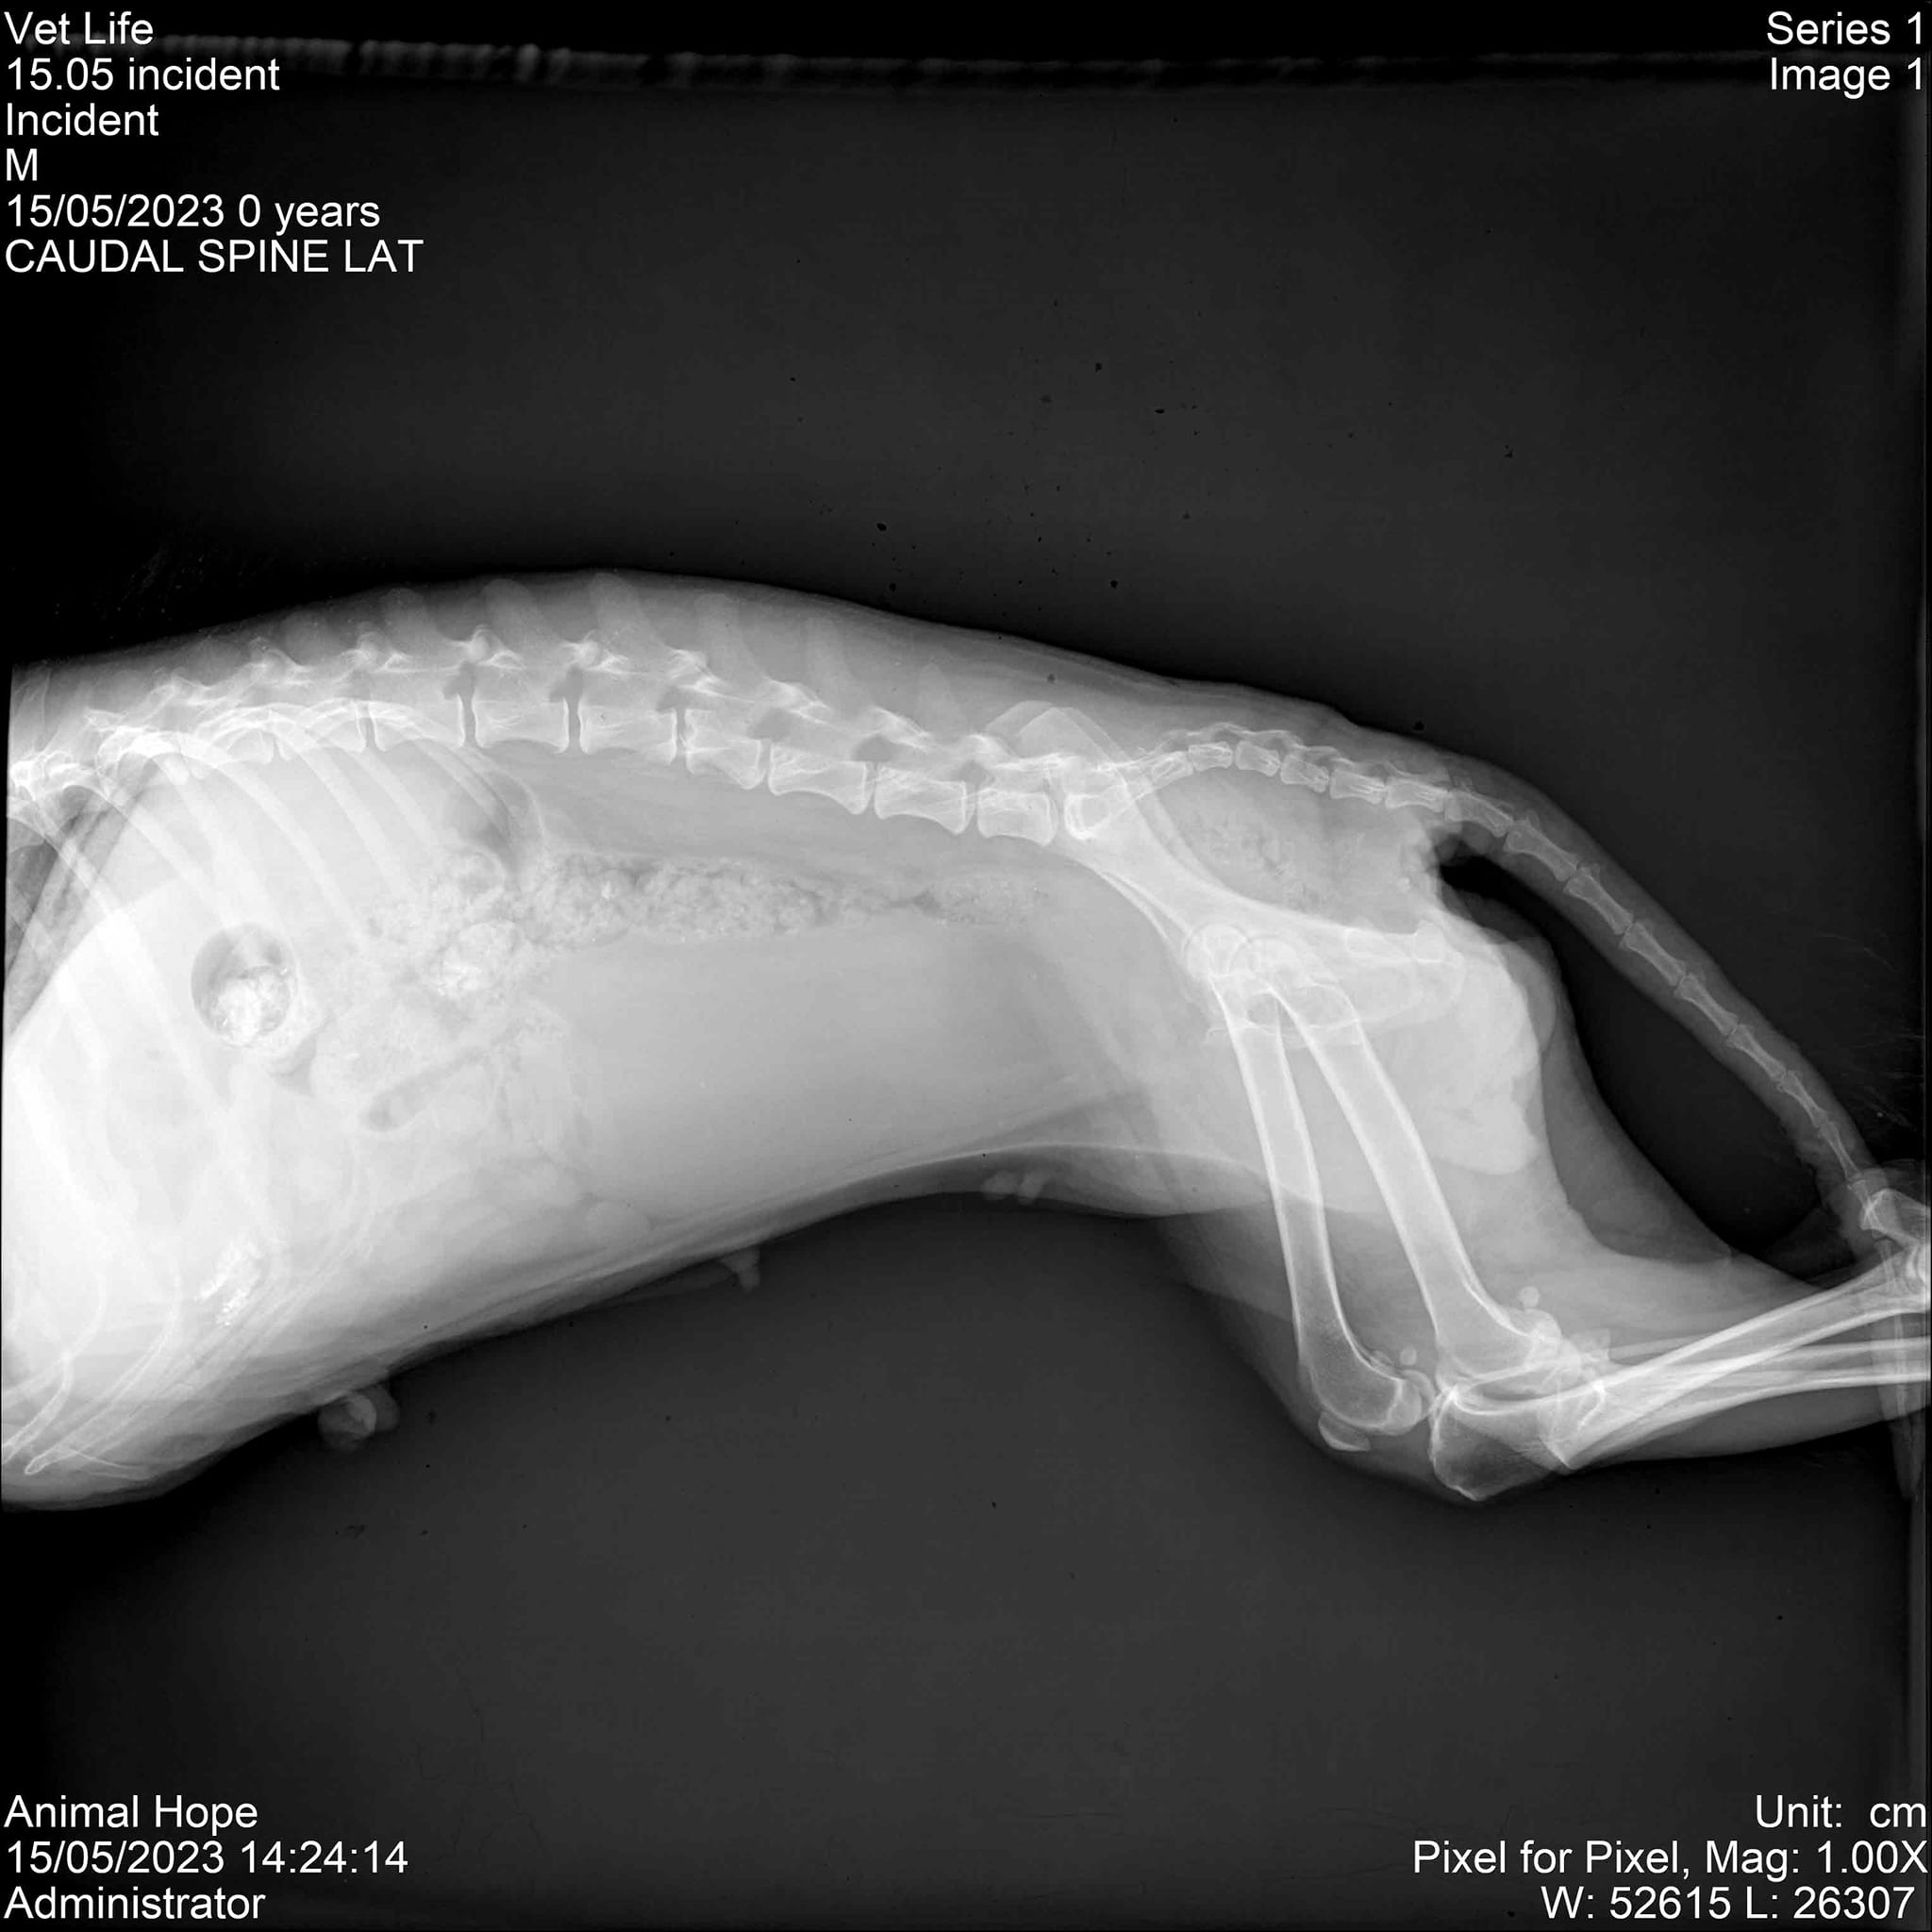

Животното е оцеляло, но е с парализирани задни крайници. Грижите за него са били поети от „Animal Hope Bulgaria – Burgas“, които са го транспортирали във варненска клиника, като по последна информация, то няма да проходи повече, но ще му бъде направена количка, с която да се придвижва. От организацията споделят:

„Оставяме баба Бубка в клиниката, където ще и бъдат направени отново кръвни изследвания, 4д тест, тест за Гана, катетаризираха я, защото задържа урина, започнаха веднага терапия за стабилизиране. След като я стабилизират, предстои операция на гръбнака за стабилизиране на прешлена. Най-вероятно няма да проходи сама повече, но ще живее и ще се придвижва с количка. На ден стационарът е 25 лева само престоя без включените медикаменти. Ще имам огромна нужда от вашата подкрепа. Може да ни подкрепите по един от следните начини: